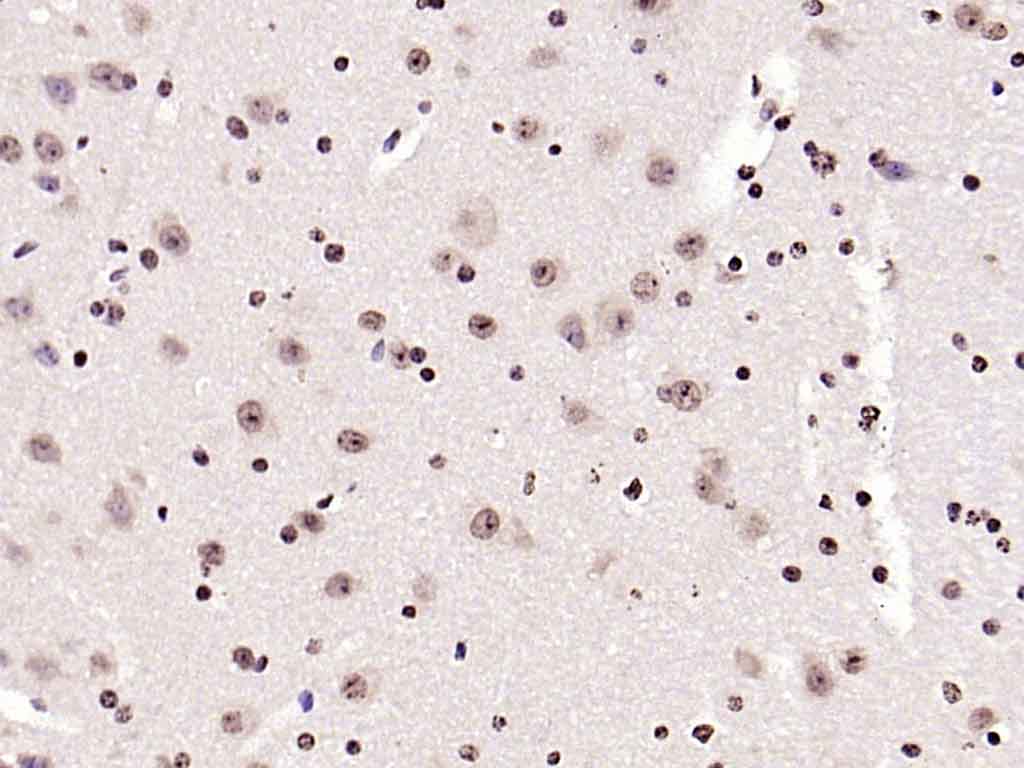

| 产品应用 | IHC-P=1:100-500, IHC-F=1:100-500, ICC/IF=1:100-500, IF=1:100-500, Flow-Cyt=2ug/Test Not yet tested in other applications. |

| {IHC-P} | {1:100-500} |

| {IHC-F} | {1:100-500} |

| {ICC/IF} | {1:100-500} |

| {IF} | {1:100-500} |